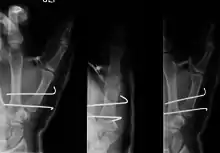

- For Bennett fractures where there is between 1 mm and 3 mm of displacement at the trapeziometacarpal joint, closed reduction and percutaneous pin fixation (CRPP) with Kirschner wires is often sufficient to ensure a satisfactory functional outcome. The wires are not employed to connect the two fracture fragments together, but rather to secure the first or second metacarpal to the trapezium.

- For Bennett fractures where there is more than 3 mm of displacement at the trapeziometacarpal joint, open reduction and internal fixation (ORIF) is typically recommended.

Regardless of which approach is employed (nonsurgical, CRPP, or ORIF), immobilization in a cast or thumb spica splint is required for four to six weeks.